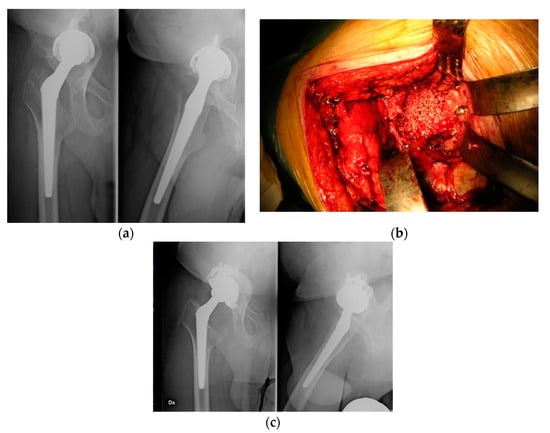

2. Materials and Methods

3. Results